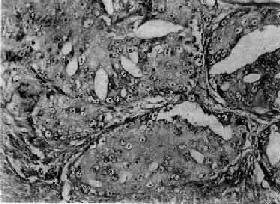

镜下,97%的前列腺均为腺,少数为移行细胞和鳞状细胞。依其分化程度可分为高分化、中分化和低分化3型。高分化前列腺最多见,细胞排列成大小不等的腺样结构,颇似前列腺增生腺体,但细胞体积较小,核较深染,上皮细胞往往呈多层排列并较不规则(图14-4),有时可呈乳头状腺或腺泡腺结构,并常可见组织向间质浸润生长;中分化腺全部或部分呈腺样结构,但腺体排列较紊乱,核异型性较明显,且有时形成筛状结构;低分化腺细胞一般较小,排列成实体团块或条索,腺腔样结构很少(图14-5)。多数病例乃由上述多种组织结构混合组成。

图14-4 前列腺(高分化型)

腺体密集,细胞体积较小,核深染,上皮细胞呈多层排列并较不规则,可见间质浸润